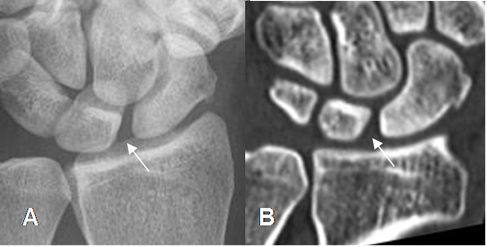

Fig 70. Ruptura del ligamento escafosemilunar.

A: Rx AP y B: TAC reconstrucción coronal. Aumento del espacio escafosemilunar, por lesión ligamentaria.